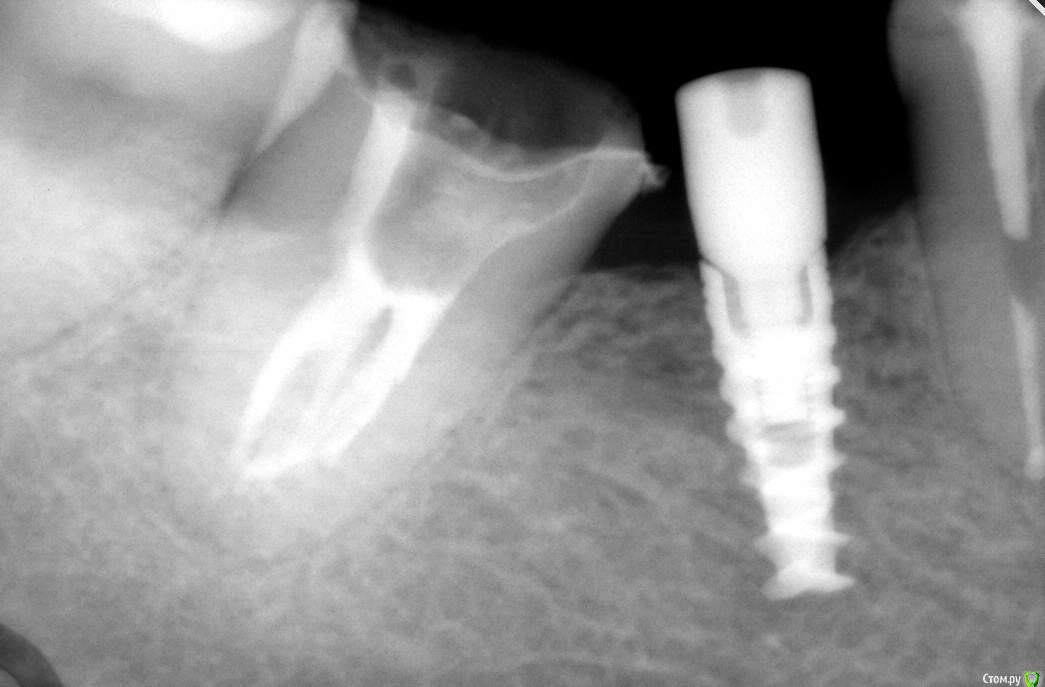

КДБ Опубликовано 16 марта, 2016 Поделиться Опубликовано 16 марта, 2016 после реставрации зуба шахта импл не позволила Вам установить ФДМ в правильное положение и вкрутили его с усилием под углом(((. Убирайте реставрацию,оценивайте состояние "внутренностей" имплантата и поступайте по ситуации. Ссылка на комментарий

simpsons Опубликовано 16 марта, 2016 Автор Поделиться Опубликовано 16 марта, 2016 после реставрации зуба шахта импл не позволила Вам установить ФДМ в правильное положение и вкрутили его с усилием под углом(((. Убирайте реставрацию,оценивайте состояние "внутренностей" имплантата и поступайте по ситуации.После того ,как я увидел,что формирователь идет под углом,то снял временную коронку и поставил в правильное положение его. Усилие в первый раз было небольшое. Ссылка на комментарий

Большой Зеленый Опубликовано 16 марта, 2016 Поделиться Опубликовано 16 марта, 2016 Не надо ничего укорачивать. Формирователь выкрутить ,а резьбу внутри скромсать фрезой для снятия коронок ,только очень плавно и нежно. Дальше слепок и техникам.. Ссылка на комментарий

simpsons Опубликовано 16 марта, 2016 Автор Поделиться Опубликовано 16 марта, 2016 Не надо ничего укорачивать. Формирователь выкрутить ,а резьбу внутри скромсать фрезой для снятия коронок ,только очень плавно и нежно. Дальше слепок и техникам.. Зеленый,попробовал на моделе укоротить винт и все получилось!теперь главное, что бы во рту получилось! Ссылка на комментарий

simpsons Опубликовано 16 марта, 2016 Автор Поделиться Опубликовано 16 марта, 2016 Можно без набора Круто!!!! Спасибо, Антон!!!! Вот как раз на такую длину и укоротил! Ссылка на комментарий

simpsons Опубликовано 16 марта, 2016 Автор Поделиться Опубликовано 16 марта, 2016 Но лучше не укорачивать,а как Антон показал,сгладить витки! Ссылка на комментарий